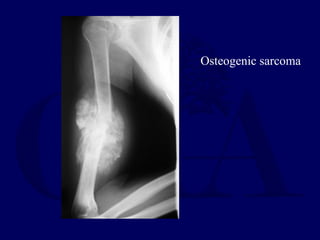

Osteogenic sarcoma

Malignant Pathologic Fractures

• May need immediate amputation

• OGS - some fx may heal during

neoadjuvant chemotherapy